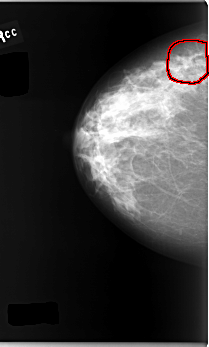

C_0095_1.RIGHT_CC

FILE: C_0095_1.RIGHT_CC.OVERLAY

TOTAL_ABNORMALITIES 1

ABNORMALITY 1

LESION_TYPE MASS SHAPE IRREGULAR MARGINS SPICULATED

ASSESSMENT 4

SUBTLETY 3

PATHOLOGY MALIGNANT

TOTAL_OUTLINES 1

BOUNDARY